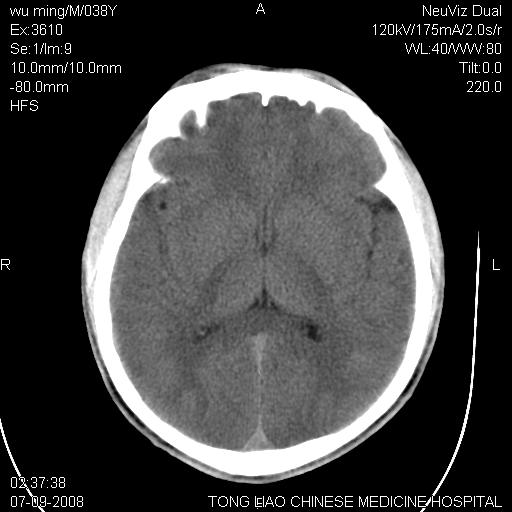

考虑:面骨、颅底骨多发骨折,颅内高压(脑肿胀)。

面骨、颅底骨多发骨折,右侧硬膜下小血肿,弥漫轴索损伤,死亡原因可能是多种因素致。

不除外轴索损伤

颅底骨折,窦腔内积血。考虑死亡原因为脑水肿压迫脑干或因大量失血死亡。

前颅窝颅底骨折,死的原因应该从头部来看不用说就是重度颅脑损伤。

考虑:面骨、颅底骨多发骨折。从五楼摔下还伤着头了,不死才怪;估计有弥漫性轴索损伤。